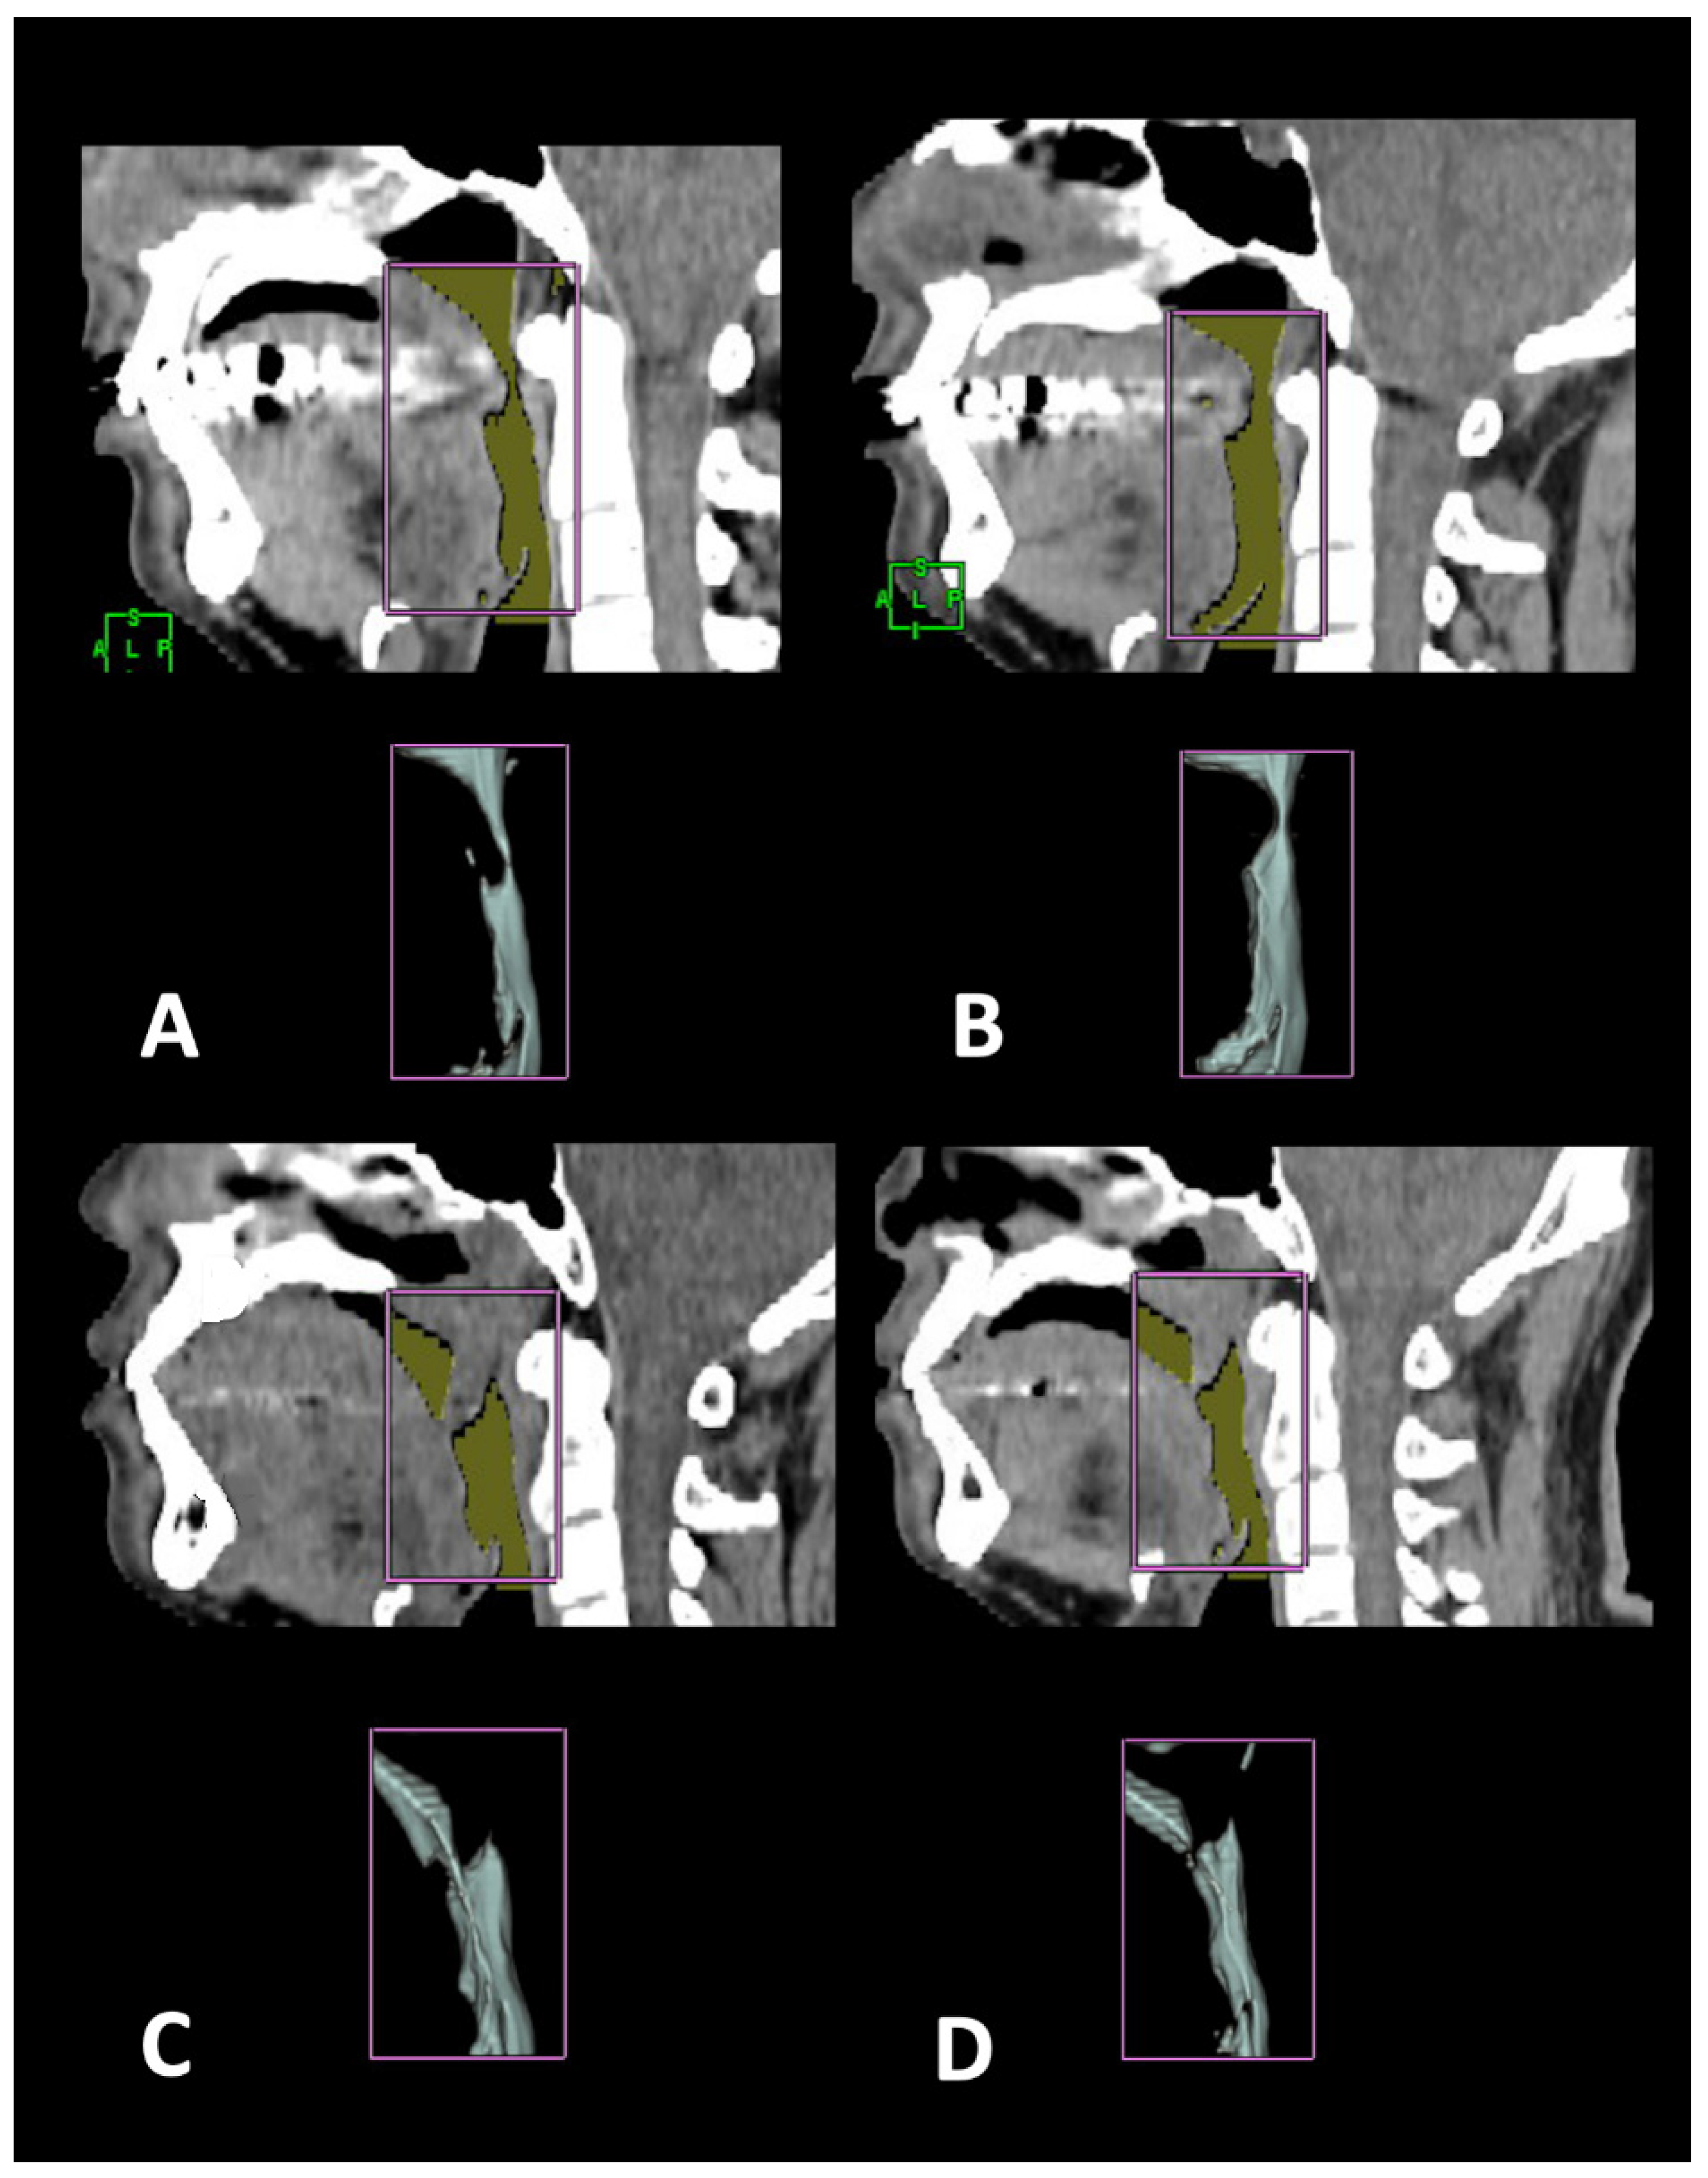

2.5. Surgical Plan and Design for Coblation Whole Tongue Surgery

2.6. Statistical Analysis